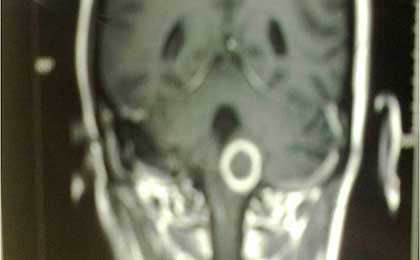

Tuberculoma of cervicomedullary region

• Tuberculoma of cervicomedullary region